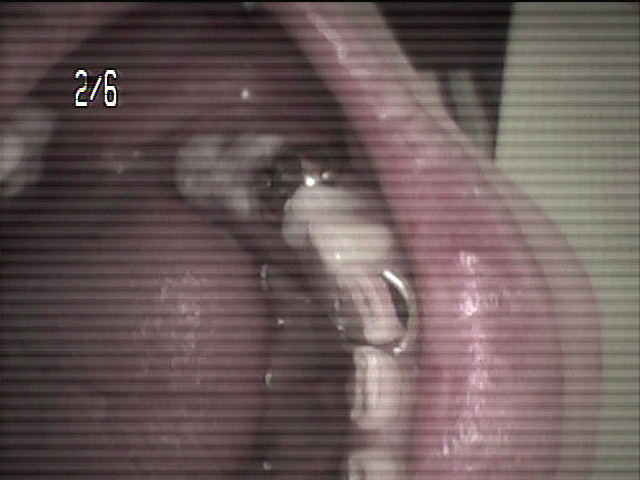

本日、出来上がりました自費の部分入れ歯ー下顎メタルプレートの症例です。

81歳の女性OUさんはとけも若々しいかたで、上下ともに、ぶぶん入れ歯ですが、今回は下顎の左右の奥歯のメタルプレートの入れ歯を新しく作りました。

自費によるメタルプレート義歯で、薄く丈夫な義歯として、とても舌感の良好な状態にすることができ、さらに自由な義歯の設計ができるため、残っているはにかける針金は白金加金で作成し、残存歯にやさしい設計となっており、舌に触れるバー部分はコバルトクロム合金で、丈夫に薄く作ってあります。

(参考代金;30万円)